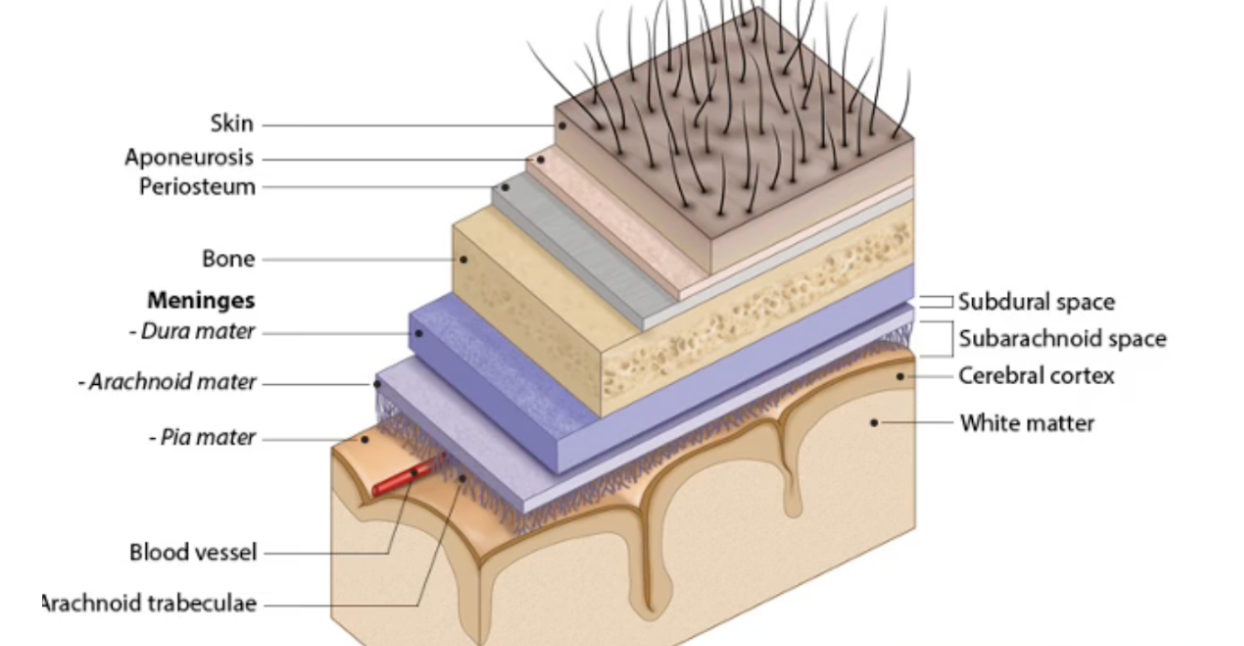

List the protective layers of the brain from outer to inner.

(1)Skin

(2)Cranial bone

(3) Cranial meninges

(4)Cerebrospinal Fluid (CSF)

What are the three layers of the Cranial Meninges (thickest to thinnest)?

Dura Mater,Arachnoid Mater, Pia Mater

Which meningeal layer is thick, fibrous, provides physical protection, and is where brain bleeds occur when damaged?

The Dura Mater.

Which meningeal layer is thin, fibrous, looks like a web, and contains the cerebrospinal fluid (CSF)?

The Arachnoid mater

Where is the CSF located relative to the Arachnoid mater?

In the Subarachnoid space

Which meningeal layer is very thin, the deepest layer, and follows all the grooves of the brain?

The Pia mater.